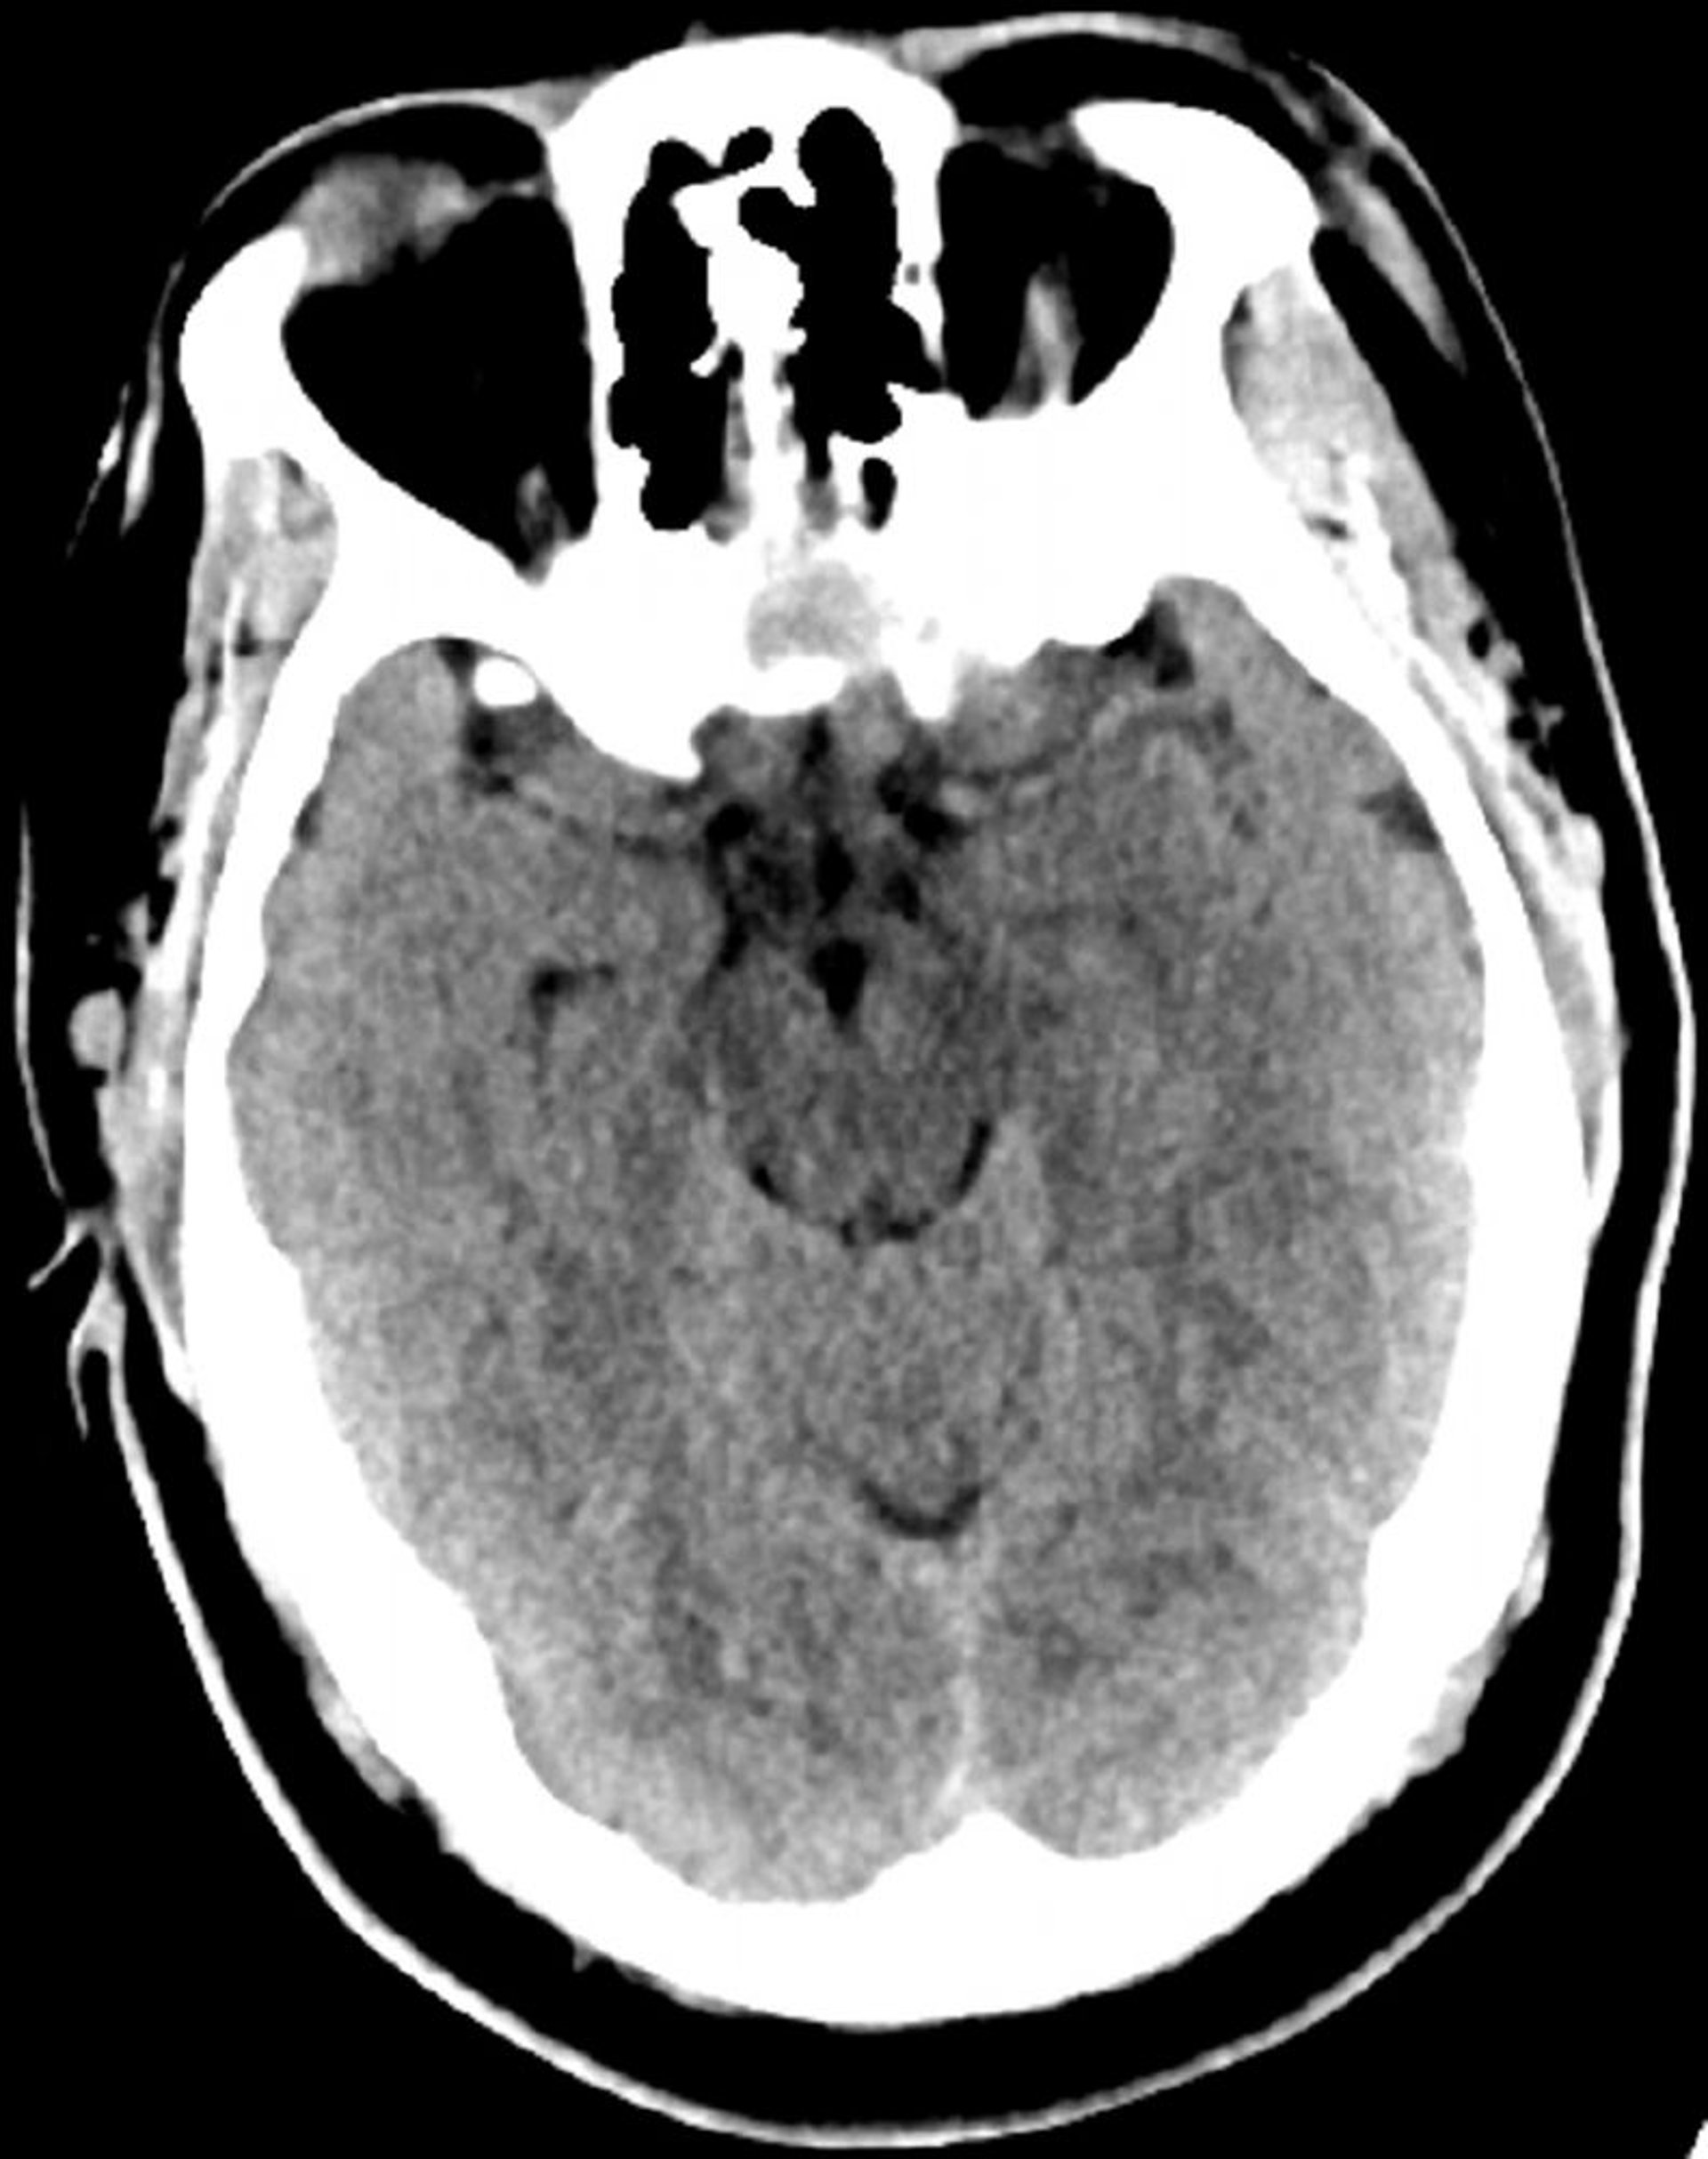

Tomodensitométrie normale de la tête (adulte, 30 ans) – Diapositive 6

Cette image est une TDM normale de la tête d'un jeune adulte âgé de 30 ans. Il n'y a pas de liquide intra- ou extra-axial ou d'hémorragie. La différenciation gris-blanc est préservée. La taille du ventricule et la forme des sillons semblent normales.